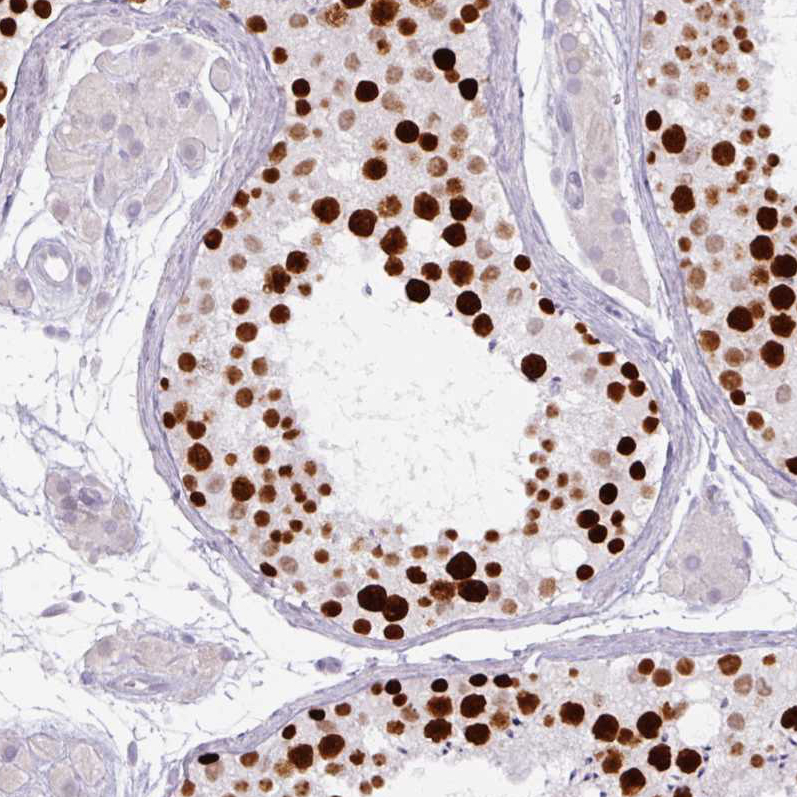

Immunohistochemistry analysis in human testis and skeletal muscle tissues using AMAb90541 antibody. Corresponding ATAD2 RNA-seq data are presented for the same tissues.